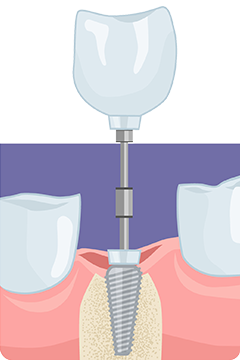

上部構造

セラミックなどで作製した人工歯を、インプラントの上に装着します。天然歯のような見た目と機能を担います。

アバットメント

上部構造とインプラントを連結する部品です。人工歯を支える支台の役割を果たします。

インプラント

歯槽骨に埋め込むチタン製の人工歯根です。骨との結合(オッセオインテグレーション)を促進する構造を持ち、インプラントの土台となります。